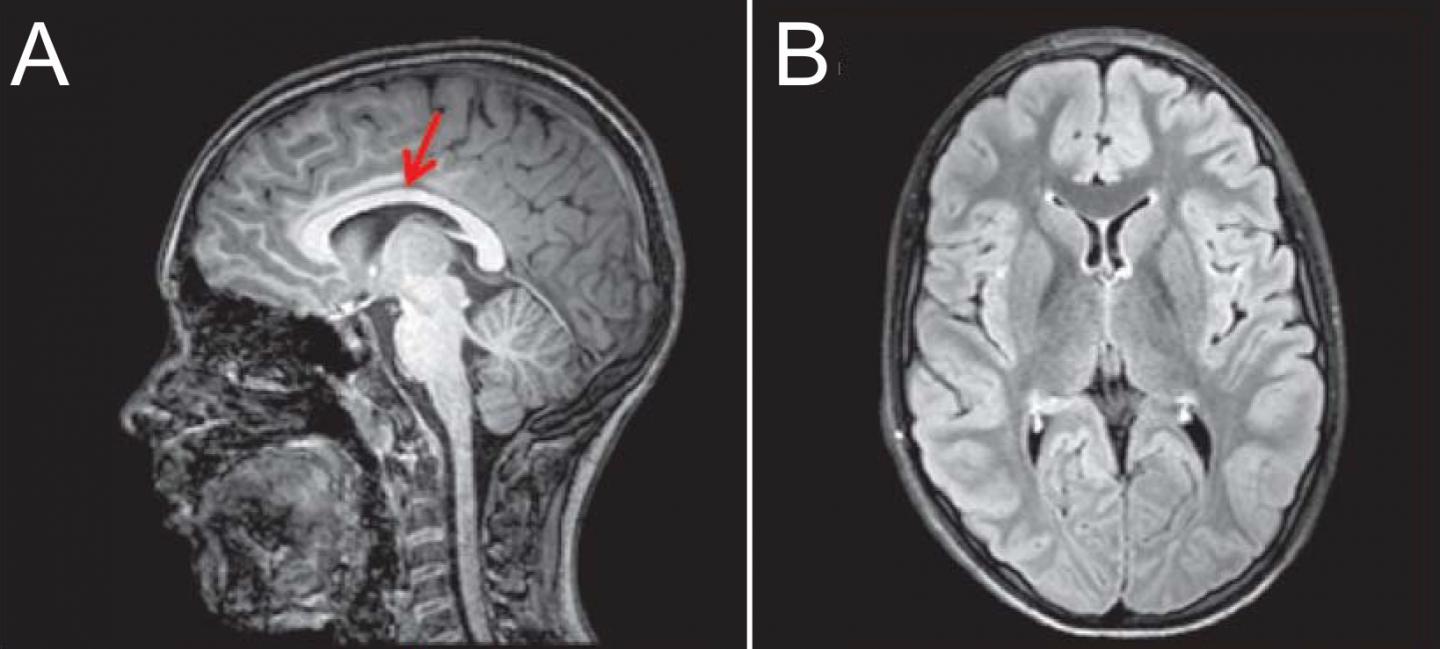

Brain imaging of a patient with a KCC3 T991A mutation. (A) T1 sequence brain MRI, midsagittal view. Corpus callosum is indicated by red arrow. (B) Fluid-attenuated inversion recovery sequence brain MRI, axial view, demonstrating normal brain volume. This material relates to a paper that appeared in the Aug. 2, 2016 issue of Science Signaling, published by AAAS. The paper, by K.T. Kahle at ale School of Medicine in New Haven, CT, and colleagues was titled, "Peripheral motor neuropathy is associated with defective kinase regulation of the KCC3 cotransporter."

Kahle <i>et al., Science Signaling</i> (2016)